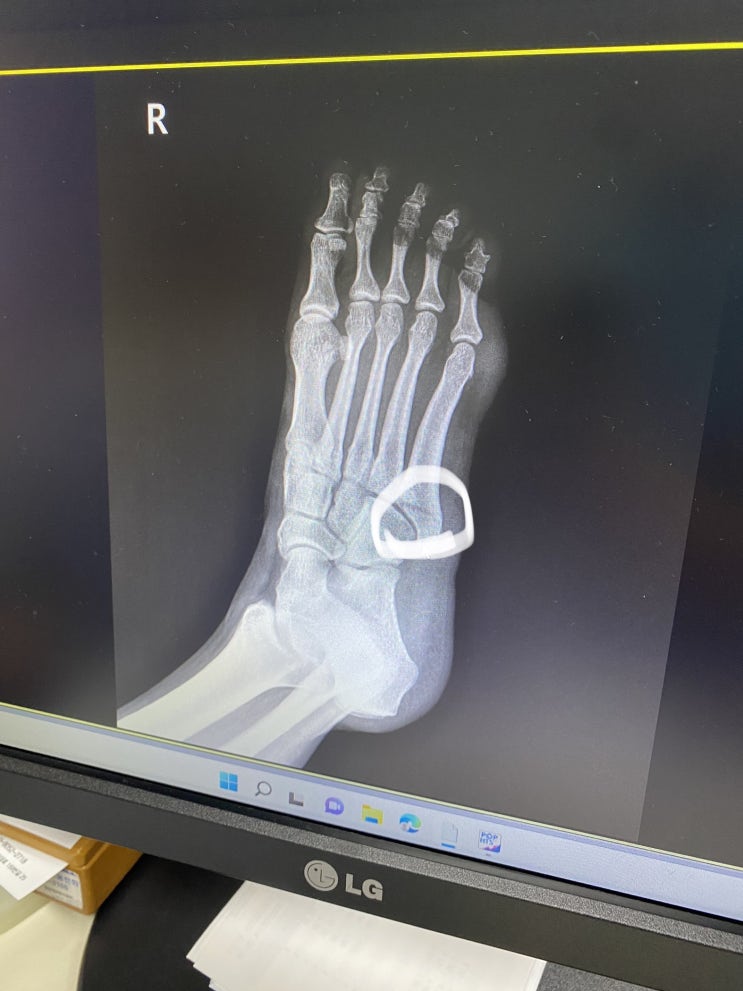

발등 골절 부이로구

2022.08.07 AM 1시쯤..? 다섯번째 발꼬락으로 타고 들어오는 발등 뼈 보이쉼? 부러줌ㅣ 골절 초6때 휠리...